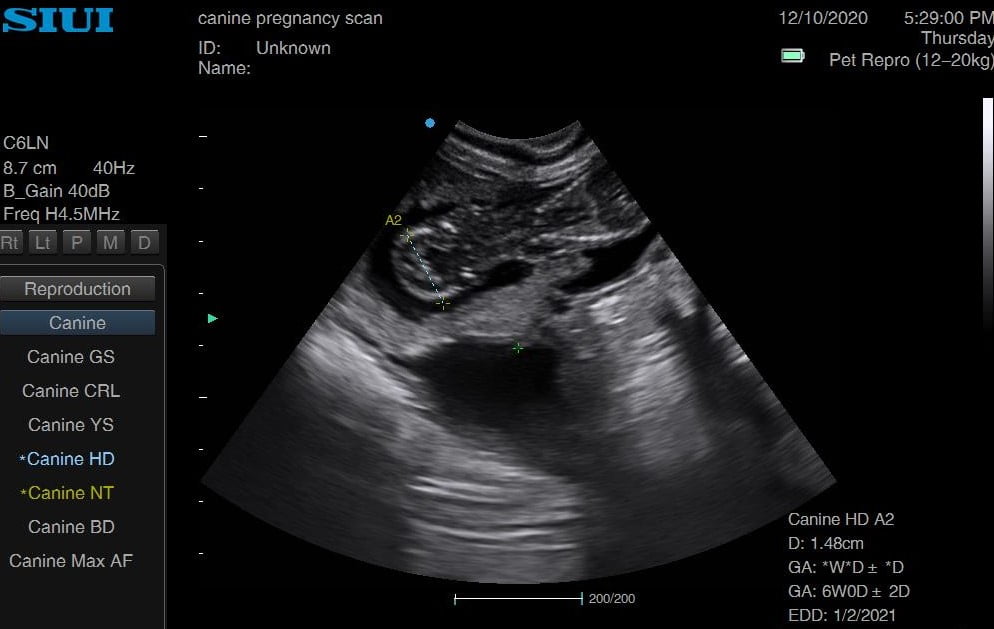

Jack Russell 6 weeks

Jack Russell already looking very rounded, head measurements at 5 weeks 6 days. She had four last litter, and we saw a minimum of four on this scan. Owners said